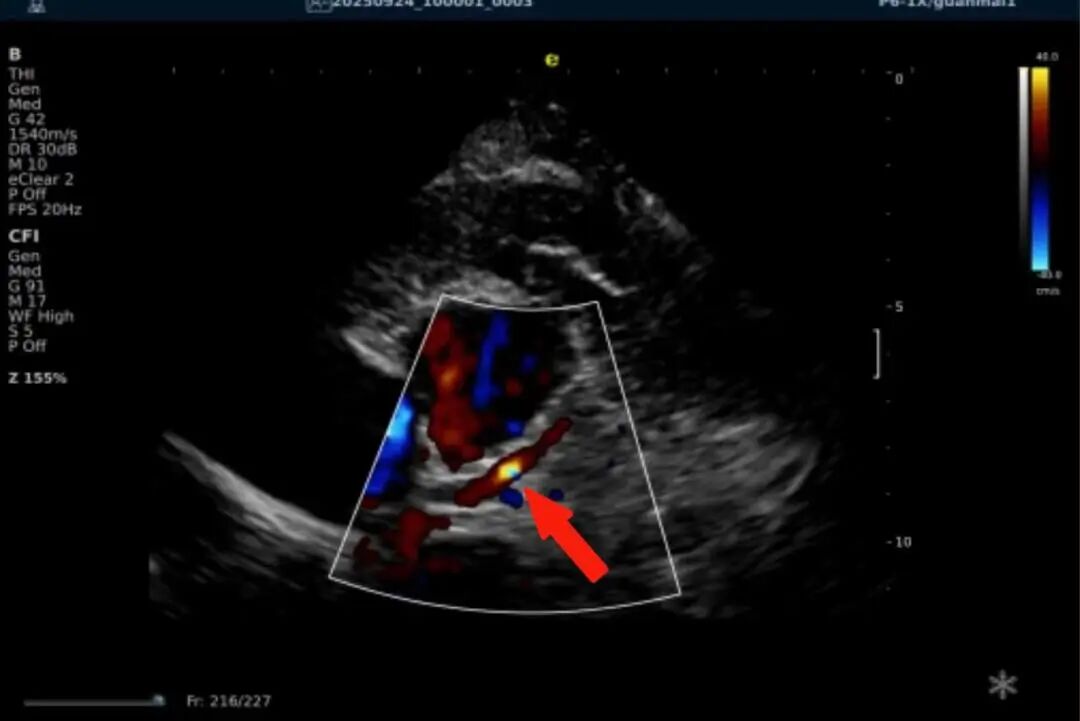

以下为逸超医疗(ESI)设备采集的冠脉图像,清晰展示了其在二维成像、彩色多普勒及频谱多普勒方面的表现:

病例实例

一、冠脉超声与CTA的协同诊断价值体现

一例胸闷患者,临床采用无创冠脉超声作为初步评估手段,检查中发现:

彩色多普勒:敏感捕捉到局部血流加速现象;频谱多普勒:测得峰值血流速度明显升高,频谱形态异常。

基于超声提示的异常发现,临床为患者安排了冠脉CTA检查,结果显示前降支近段存在约45%狭窄,与超声提示的血流动力学改变高度一致。

这一病例体现了冠脉超声作为初筛工具的重要价值:它能够无创、实时地评估冠脉血流动力学状态,为后续是否需要进一步影像检查提供重要参考。超声与CTA的协同应用,既能评估结构变化,又能反映功能状态,为临床诊断提供了更全面的信息。